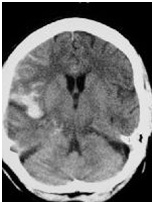

Epidural hematomas are typically associated with middle meningeal artery injuries and are seen on CT as a lenticular hematoma. The classic presentation in adults is described as a lucid interval followed by rapid deterioration. This interval of normalcy is rare in children. Children with hematomas greater than 40 mL may require evacuation.

Subdural hemorrhages are differentiated by the age of the injury. Both acute and subacute subdural hemorrhages may occur from birth injury or abuse in infants. Crescent shaped lesions at the surface of the brain are often associated with mass effect and cortical edema. Operative intervention is indicated when neurologic decompensation occurs and a significant subdural hemorrhage is present. Acute subdural hematomas have a worse prognosis than epidural hematomas due to the underlying brain damage. Patients with a midline shift greater than 10 mm should be promptly taken to the operating room for neurosurgery evacuation.